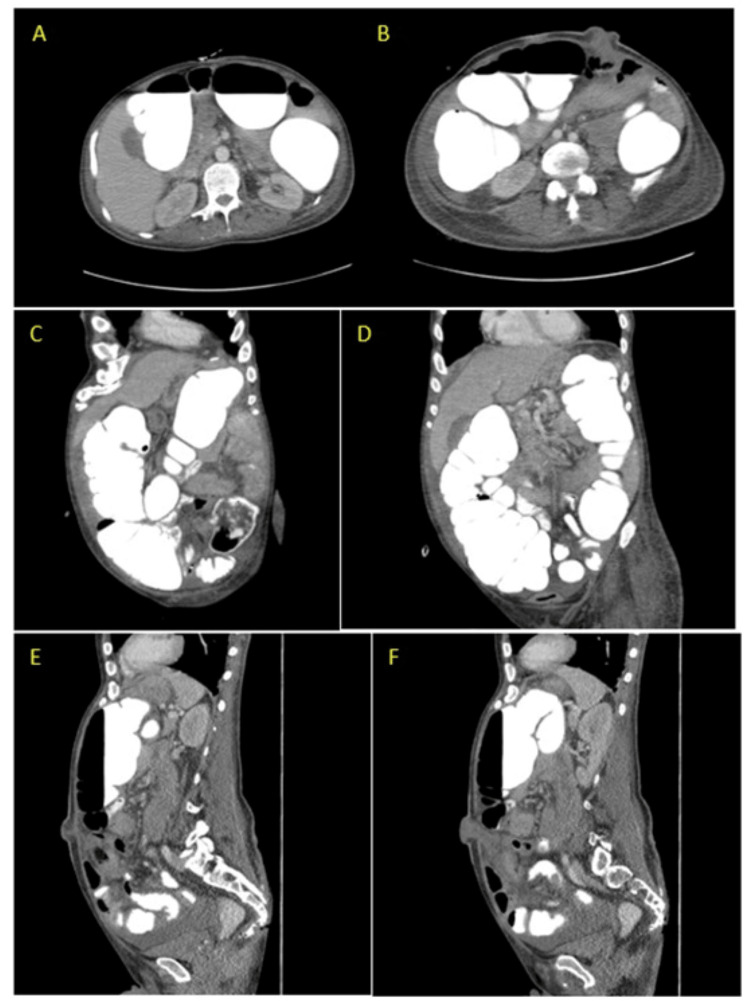

A contrast-enhanced CT scan of the abdomen and pelvis revealed normal small bowel loops and marked colonic distention with contrast throughout the colon (Figure 1). However, the patient's ostomy output remained diminished, suggesting ileus. Consequently, the patient's narcotic medications were discontinued, and he was placed on nil per os (NPO) status, with the PEG tube set to gravity for conservative management. The following day, the ostomy was digitally examined and found to be patent without stenosis or obstruction. Subsequently, the patient underwent a colonoscopy to further evaluate the ostomy site, revealing minimal fecal matter but no obstruction. A diagnosis of colonic pseudo-obstruction was established.

Figure 1. CT abdomen and pelvis with oral and IV contrast showing marked distention and colonic dilation without anatomic obstruction. Images A and B are the axial view and C, D, E, and F are the sagittal view, with E and F showing the ostomy.